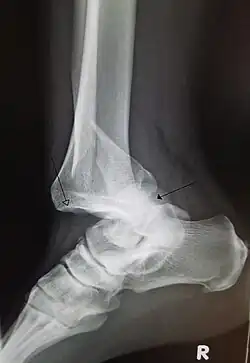

A traumatic dislocation of the tibiotarsal joint of the ankle with distal fibular fracture. Open arrow marks the tibia and the closed arrow marks the talus.

In the shoulder, vessel and nerve injuries are rare, but can cause many impairments and requires a longer recovery process.[5] Knee dislocations are rare, but can be complicated by injuries to arteries and nerves, leading to limb-threatening complications.[6] Degenerative changes following injury to the wrist are common, with many developing arthritis.[7] Persistent nerve pain years after the initial trauma is not uncommon.[7] Most finger dislocations occur in the middle of the finger (PIP) and are complicated by ligamentous injury (volar plate).[8] Since most dislocations involving the joint near the fingertip (DIP joint) are due to trauma, there is often an associated fracture or tissue injury.[8] Hip dislocations are at risk for osteonecrosis of the femoral head, femoral head fractures, the development of osteoarthritis, and sciatic nerve injury.[9][10] Given the strength of ligaments in the foot and ankle, ankle dislocation-fractures can occur.[11]

• An ankle dislocation without fracture is rare, due to the strength of ligaments surrounding the ankle.[51]